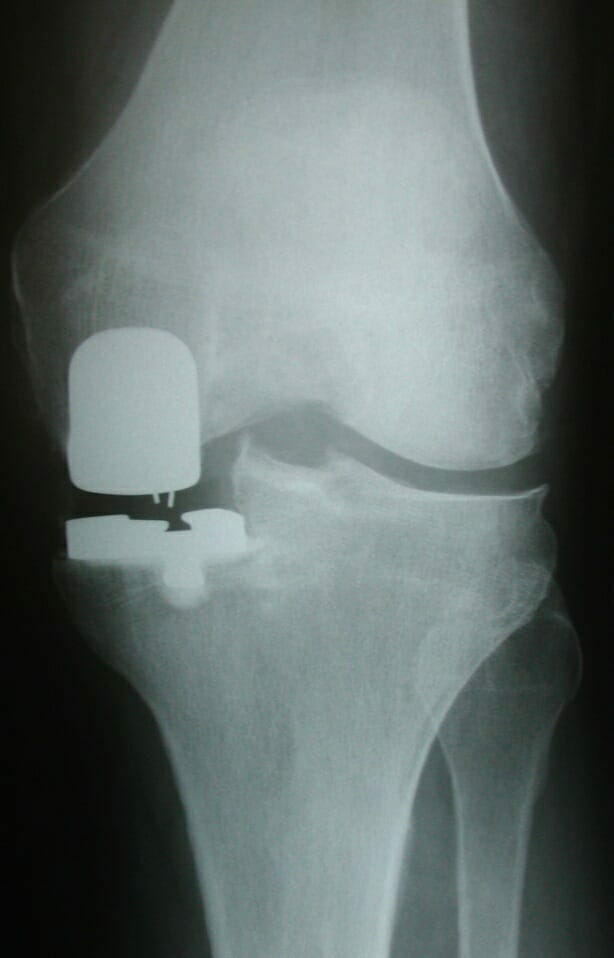

Investigations for arthritis usually entail weight-bearing radiographs of the knee and also a long leg standing alignment x-ray of the leg to show the axes of the leg and knee.

AP x-ray of the knee showing gross lateral compartment osteoarthritis with total loss of lateral joint space.